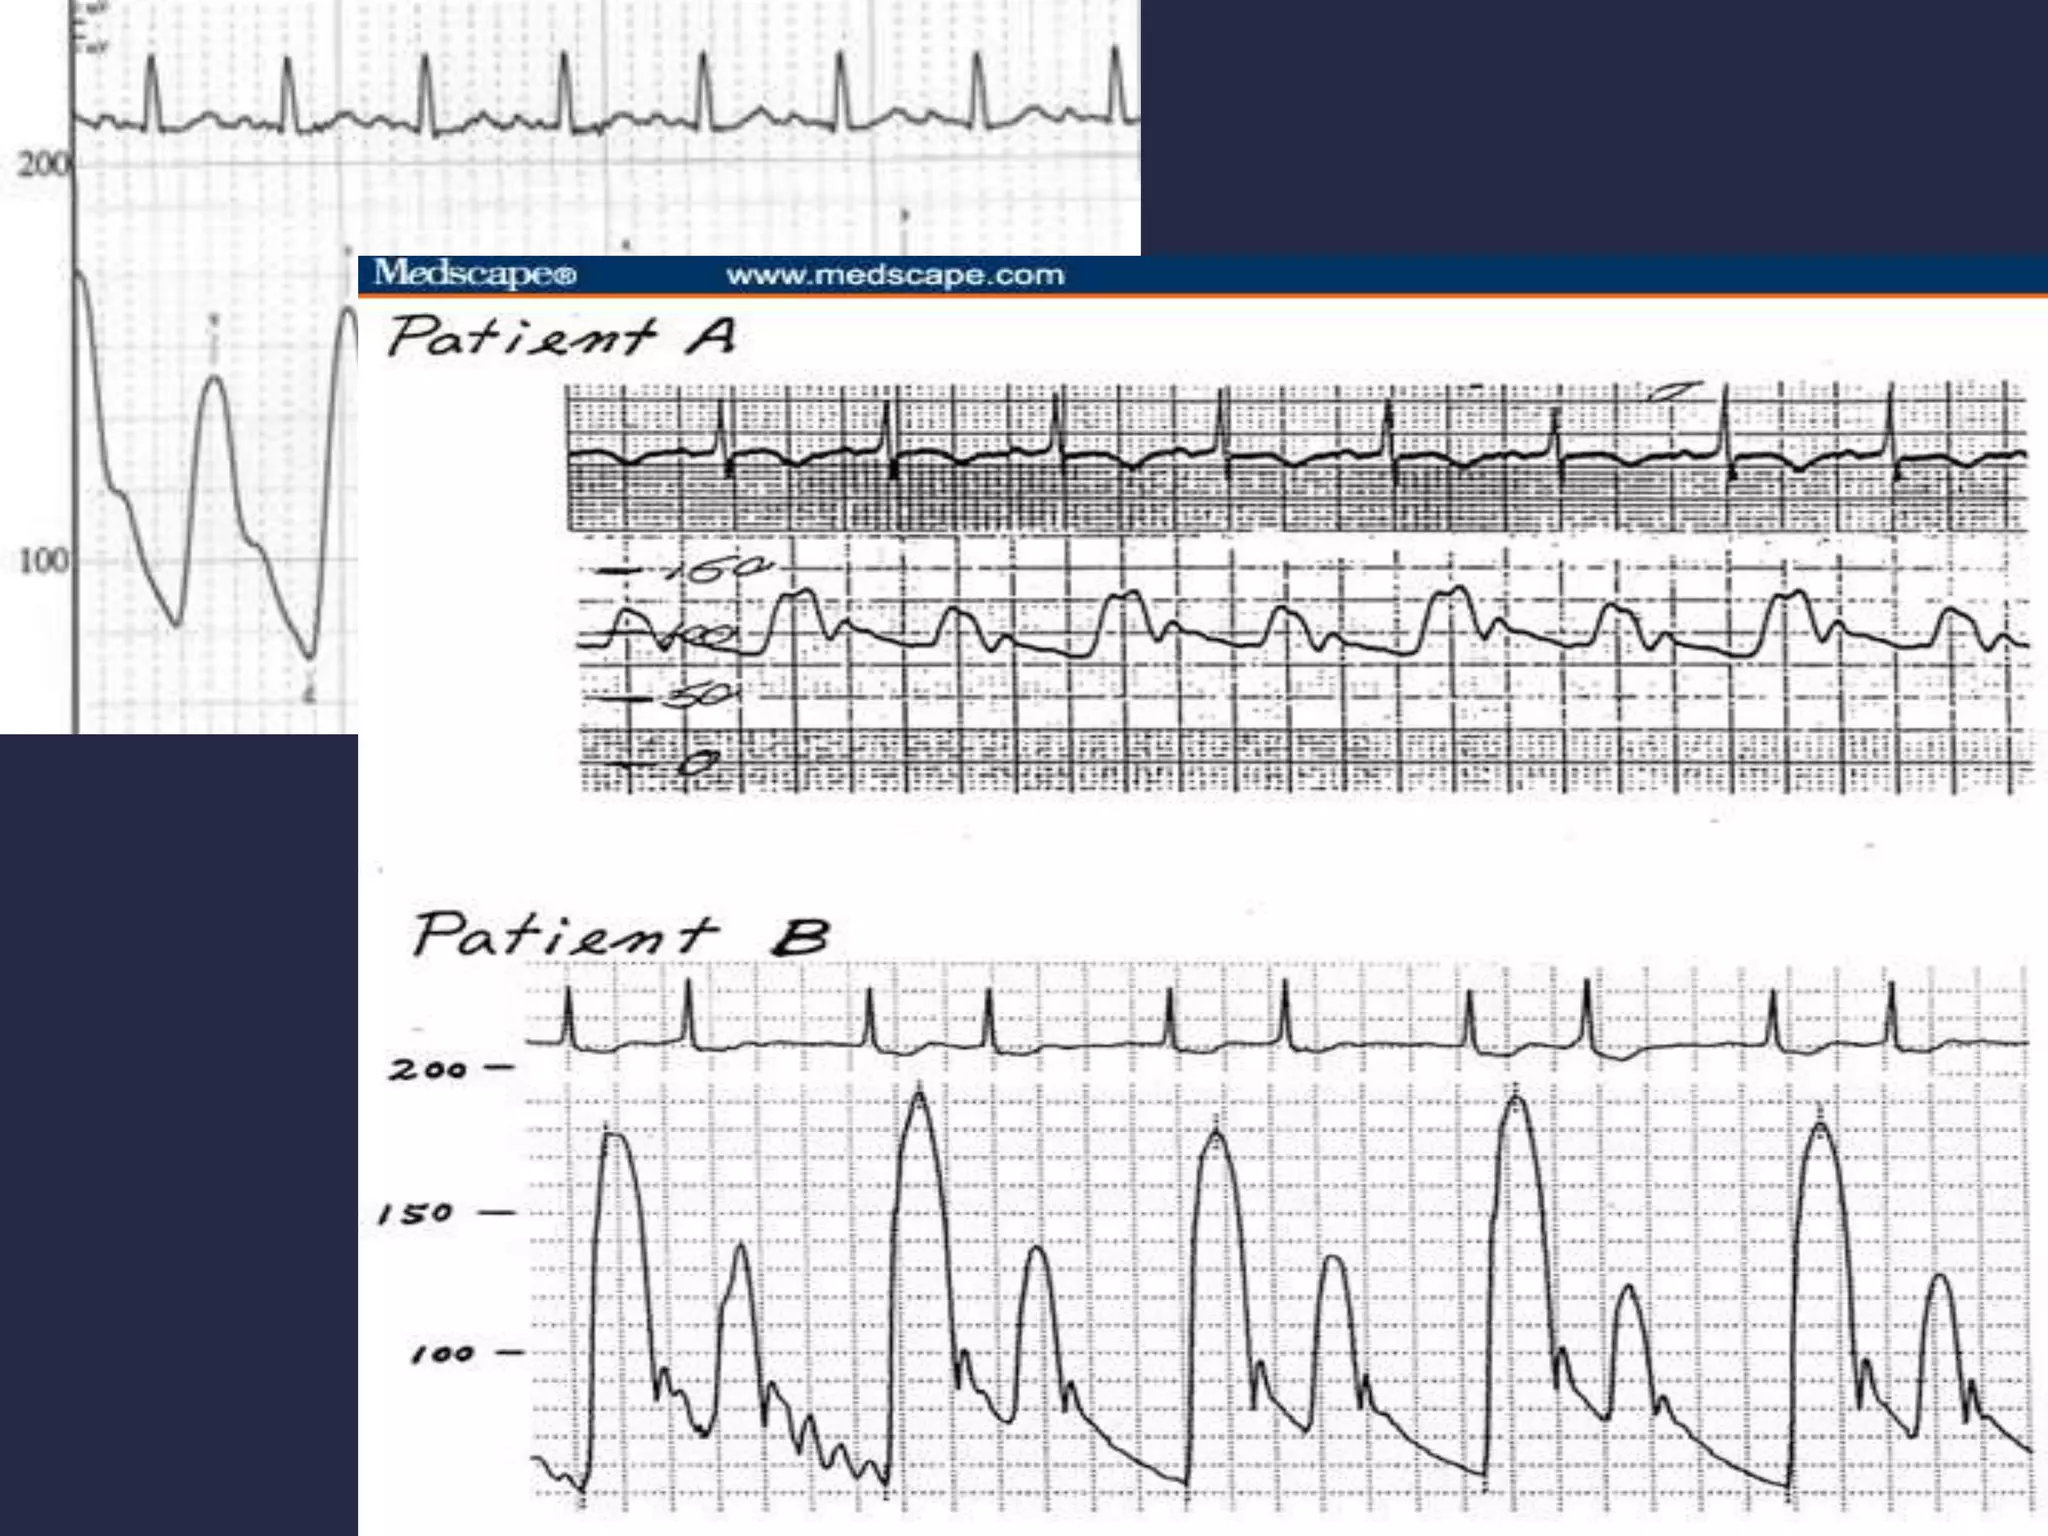

 Simultaneous LV,LA pressure tracings.

 Check zero pressures of the PCWP,FA,LV after catheters and

sheath have been flushed.

 LV pressure tracing 200mmHg scale at 50 mm/sec paper speed.

 PCWP pressure tracing 40 mm Hg scales at 50mm/sec paper

speed.

 Use 100mm/sec speed if a mitral valve gradient is present.

 Advance a pigtail into the LV.

 Check the zero pressures of both sheath and pigtail catheter

after flushing.

 Record LV and FA pressure (25mm/sec speed,200mmHg

scale)

 100mm/sec speed if an aortic valve gradient is present.

 Simultaneous LV,LApressure tracings.  Check zero pressures of the PCWP,FA,LV after catheters and sheath have been flushed.  LV pressure tracing 200mmHg scale at 50 mm/sec paper speed.  PCWP pressure tracing 40 mm Hg scales at 50mm/sec paper speed.  Use 100mm/sec speed if a mitral valve gradient is present.

 Advance apigtail into the LV.  Check the zero pressures of both sheath and pigtail catheter after flushing.  Record LV and FA pressure (25mm/sec speed,200mmHg scale)  100mm/sec speed if an aortic valve gradient is present.